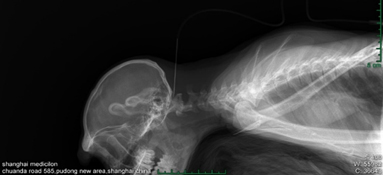

ÃÀ¸ß÷ÉúÎïÑùÆ·ÊÕÂÞ¼¼Êõº­¸Ç³¬ÉùÖ¸µ¼µÄ¸ÎÔà»îÌåÈ¡²Ä¡¢»ùÓÚÊÖÊõµÄ¸ÎÔà»îÌåÈ¡²Ä¡¢ºï²àÄÔÊÒ¸øÒ©ÒÔ¼°¾­Ñü×µ´©´ÌÄÔ¼¹ÒºÊÕÂ޵ȡ£¡£¡£¡£ÕâЩרҵ¼¼ÊõµÄÔËÓ㬣¬£¬£¬£¬£¬ÎªÒ©ÎïÑз¢ÌṩÁËÖÁ¹ØÖ÷ÒªµÄÊý¾ÝºÍ×ÊÔ´Ö§³Ö¡£¡£¡£¡£

³¬ÉùÖ¸µ¼µÄ¸ÎÔà»îÌåÈ¡²Ä.jpg

»ùÓÚÊÖÊõµÄ¸ÎÔà»îÌåÈ¡²Ä.jpg